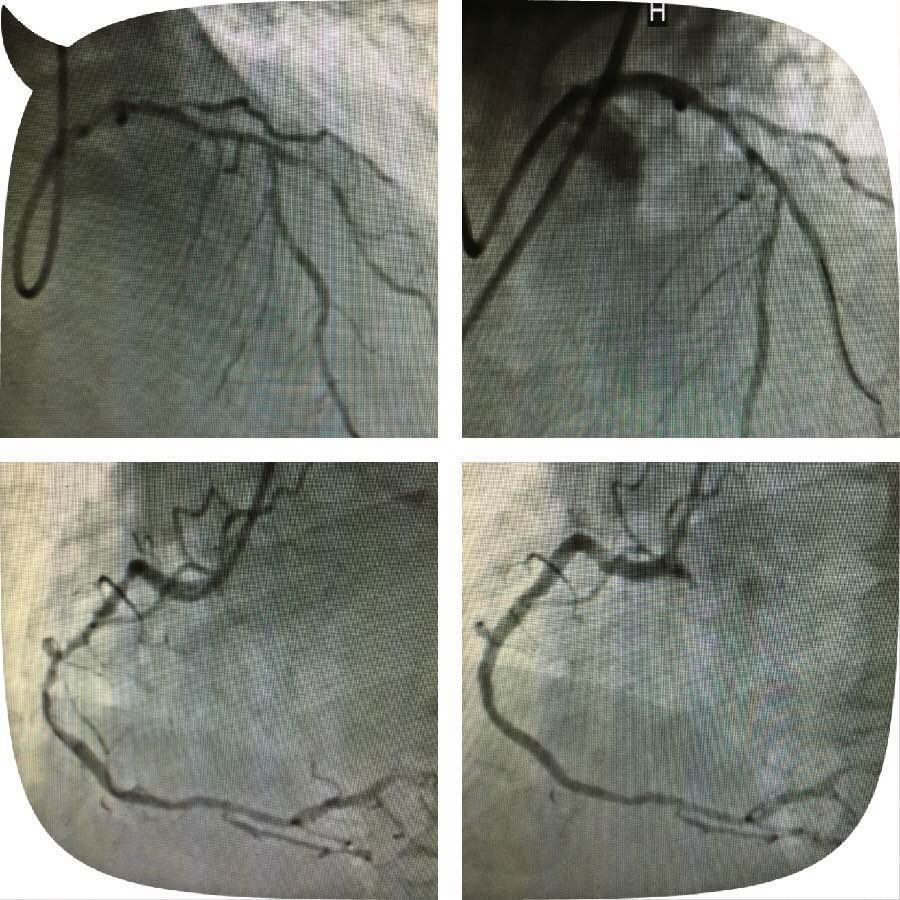

原来,这位老人突发心脏病被送到男同视频 心五病区,入院后心电图示非ST段抬高心肌梗死,急诊行冠状动脉造影检查发现左主干钙化严重狭窄,合并右冠脉钙化严重狭窄病变,死亡风险极高。考虑患者病变复杂,贸然行左主干介入治疗风险极高,针对此患者特殊情况,心血管病医院组织专家进行缜密讨论,并与患者及家属充分沟通交流后,制定了血运重建的合理治疗方案。首先完成患者右冠脉钙化并严重狭窄病变的介入治疗,再次应用切割球囊行左主干严重钙化狭窄病变和对角支严重狭窄病变的介入治疗。

实施右冠严重狭窄长病变的介入治疗一周后,患者病情稍有缓解,经心血管病医院专家的缜密讨论,拟行切割球囊治疗患者的左主干钙化并严重狭窄病变,手术由心五病区郭瑄主任及陆艳副主任医师实施。术中如预期情况一样,经普通球囊反复扩张后,左主干的狭窄仍显得“纹丝不动”,患者出现胸痛症状,手术时间延长一分,患者手术风险增加十分,这时应用切割球囊就是关键的利器。手术成功!术中患者各项生命体征平稳,安返病房。